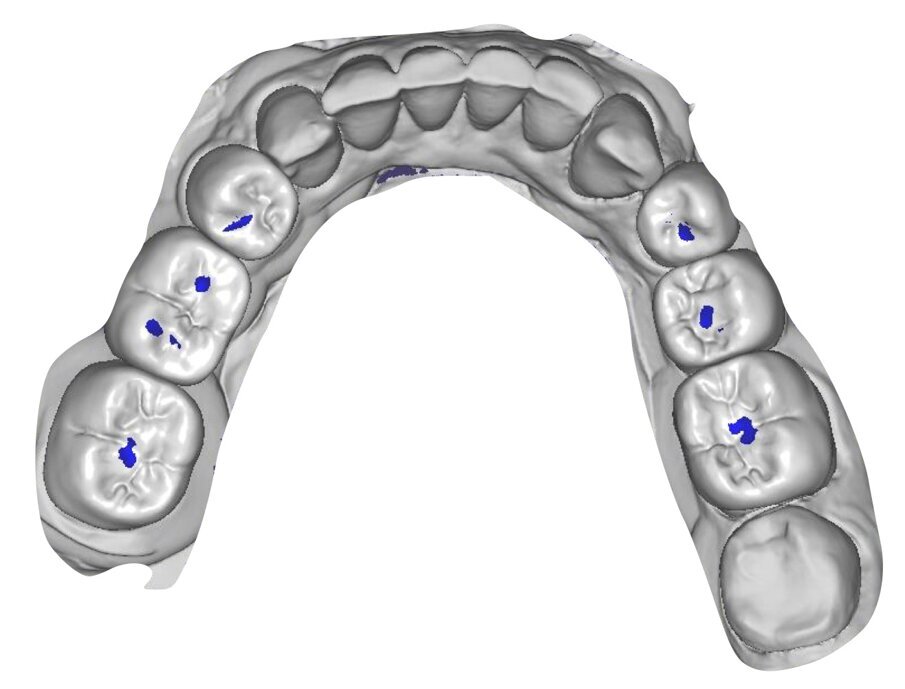

I modelli sono così importati in corretta posizione spaziale tramite il modulo exocad Virtual Articulator (Fig. 25). Non avendo a disposizione nel CAD l’analogo virtuale dell’articolatore Reference SL, viene impostato il sistema virtuale SAM, che usa lo stesso piano di riferimento axio-orbitale e geometria sovrapponibile al Reference SL. Per la programmazione virtuale dei parametri funzionali dell’articolatore si riesegue l’output dall’axiografia elettronica con Gamma Dental per SAM (Fig. 26). Si procede perciò ora con la modellazione CAD della ceratura mantenendo il riferimento dato dal piano occlusale individuato dai coni di centrica scansiti con l’articolatore (Fig. 27). L’articolatore virtuale consente una prima verifica dei rapporti occlusali tra gli elementi e un abbozzo di funzionalizzazione delle cuspidi con strumenti virtuali dinamici, che permette di arrivare ad un CAD design vicino alla morfologia ricercata (Figg. 28-33). Il modellato è ora fresato in cera Yeti Dental al CAM con fresatore VHF Cam5-S1 ed i denti in cera, tutti singolarmente sfilabili, sono posizionati sui modelli eseguiti con stampa 3D.

Il fresato ottenuto è poi riportato su articolatore Reference SL – già opportunamente programmato – e viene dall’Odontotecnico competente più precisamente funzionalizzato secondo i criteri della programmazione funzionale sequenziale, evidenziando con cere colorate i rapporti di centrica, le funzioni di mediotrusiva e protrusiva e le protezioni retrusive. I monconi sfilabili consentono la modellazione della sequenzialità mediotrusiva con la guida incisale indicata dalla registrazione axiografica (blu) (Figg. 34-37). La ceratura sequenziale è ora scansita con Sirona InEos X5 su Exocad, ed il modellato viene ricontrollato al CAD per spessori, connessioni e morfologia, e nella regolazione degli offsets per la ripreparazione dei monconi, ed è inviato al CAM per la fresatura dei II provvisori in Bredent breCAM.multicom, un PMMA con microriempitivo ceramico ad alta stabilità, su Dental Plus 5 Axis Milling Machine. La rifinitura dei monconi è seguita da ribasatura dei II provvisori in TRP - previo isolamento di tutte le superfici funzionali - e gli stessi sono poi rifiniti e lucidati. I soli elementi 3.3, 4.2 e 4.3 sono rimodellati in regione incisale con addictions in composito, secondo la morfologia studiata in ceratura. La consegna conferma la buona integrazione dei manufatti dal punto di vista estetico, occlusale, articolare e neuromuscolare, con controllo occlusale conforme al progetto (Figg. 38-42).

Il paziente utilizza questi secondi provvisori per otto settimane, durante le quali conferma la buona integrazione dei restauri e la soddisfacente funzione occlusale. Ciò è verificato con l’esecuzione di una nuova axiografia elettronica che già a due settimane dalla consegna evidenzia una buona risposta muscolare al nuovo design occlusale ed alla nuova postura mandibolare in TRP (Figg. 43-46). Provvediamo infine alle impronte per la costruzione dei manufatti definitivi in Zirconia-ceramica. I modelli sono scansiti in laboratorio con inEos X5 (Dentsply Sirona) su exocad (Figg. 47-49), ed una seconda scansione viene eseguita con i provvisori del Paziente posizionati sui modelli (Figg. 50-52). Il CAD consente di eseguire un matching fra le due scansioni, per cui i secondi provvisori utilizzati in TRP, con funzione occlusale sequenziale già completamente programmata, sono utilizzati per definire le morfologie dentali definitive di tutti gli elementi da restaurare (Figg. 53, 54) secondo il rapporto intermascellare definito (Figg. 55-58). Si esegue quindi fresatura al CAM della protesi definitiva in zirconia (Figg. 59, 60), la stratificazione e finitura ed infine la consegna al Paziente con cementazione in Panavia V5 (Figg. 61-65).